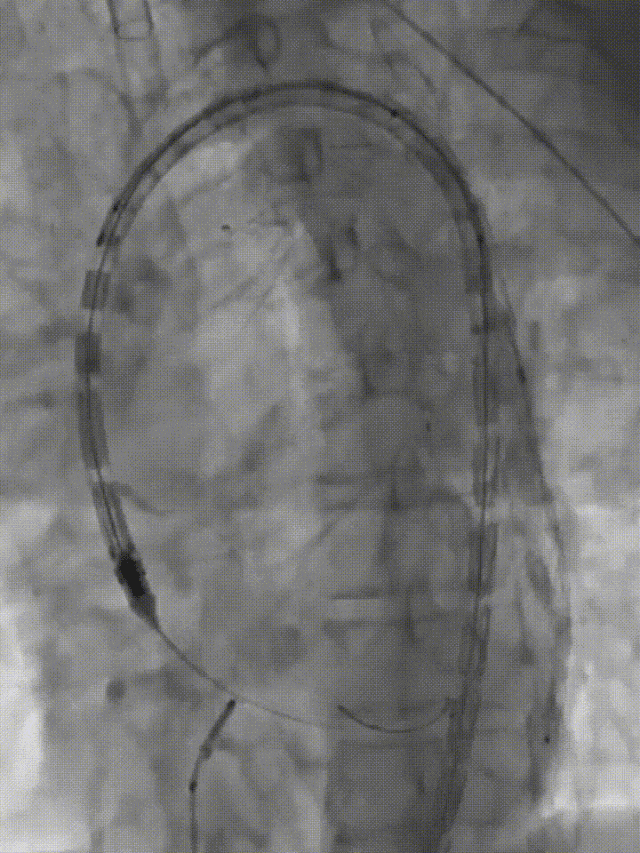

术前影像

造影后经股动脉导入并释放限制支架

经股动脉导入主体支架,抓捕无名动脉预留导丝,支架导入升主动脉

造影定位后释放主体支架

经股动脉依次超选导入分支支架,释放并球囊扩张,术毕造影

术后复查

三个穿刺点(双侧肱及单侧股动脉)无需颈部切口/穿刺